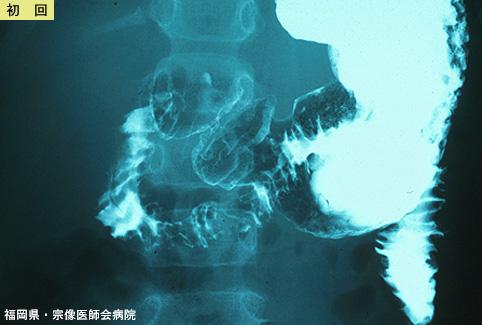

복통, 설사, 구토를 동반한 Schonlein-Henoch 자반병 (증례제시:후쿠오카현, 무나카타의사회병원 방사선과, Dr. 요시다)

[Image-ID:5566]

염증성 및 궤양성질환/Schonlein-Henoch자반병

십이지장/2개 이상

X-P